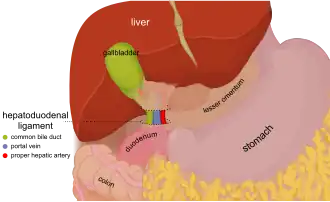

In this image, the hepatogastric ligament is labeled the lesser omentum, which it is part of. The hepatoduodenal ligament is a separate ligament that is also part of the lesser omentum. | |

The hepatogastric ligament or gastrohepatic ligament connects the liver to the lesser curvature of the stomach. It contains the right and the left gastric arteries. In the abdominal cavity, it separates the greater and lesser sacs on the right. It is sometimes cut during surgery in order to access the lesser sac. The hepatogastric ligament consists of a dense cranial portion and the caudal portion termed the pars flaccida.